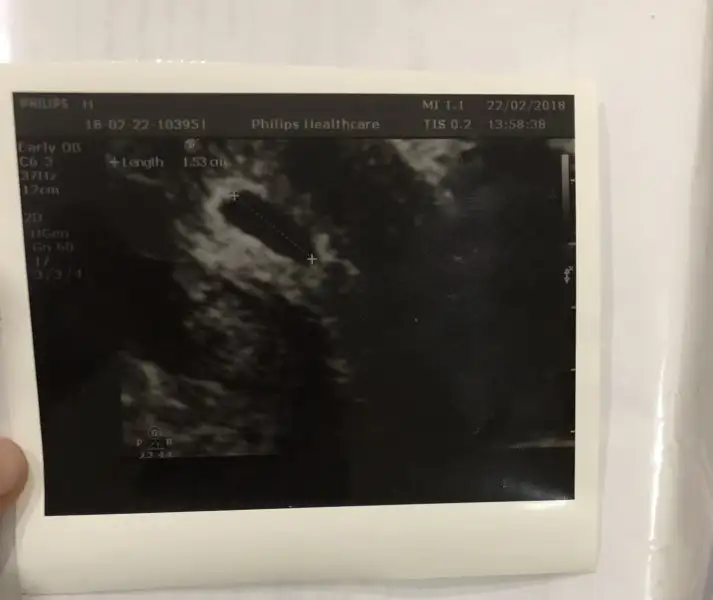

Yazar canım ben sana örnek benim ultrasonu atim bak 1.53cm yazıyo evet aslında bende sordugumda sarı akıntıyı olur demişti doktor inşallah sorun yoktur bu lekelenmeden sonra

Canım valla baktım da şimdi benimkinde keseyi ölçmemiş olcak ki kağıtta yazmıyo..sen kese ölçüsünü dikkate alma kaç hafta kaç günlük oluyorsun Çarşamba randevuya gideceğin gün ?